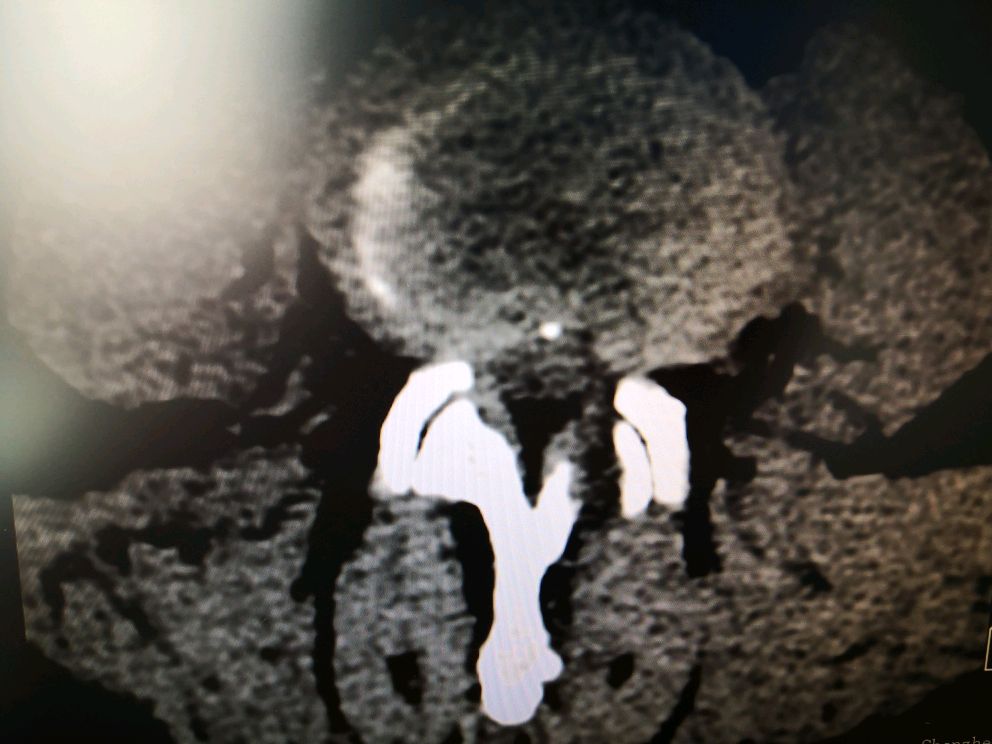

经人介绍到我科就诊,经查体,诊断为腰椎间盘突出症,如图:腰3/4椎间盘突出并重度脱垂游离,难怪疼痛那么剧烈!

其他节段也有突出,并且腰椎侧方滑脱,是钉棒内固定术还是微创内镜单纯摘除髓核?我们仔细查体发现主要矛盾还是脱出的髓核,患者也不愿意行切开内固定术,于是,采用了脊柱内镜微创手术!

脊柱内镜,椎间盘髓核无处藏身!不但好,而且好!